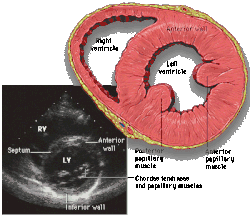

![]() Parasternal long axis |

![]() Parasternal short axis |

| Each figure contains a TTE with a black background, and a corresponding colored illustration. | Patrick J. Lynch and C. Carl Jaffe, Yale University, 2006. | ||||||||||

| Click on a figure to enlarge it and see some parts of the heart identified. RV, right ventricle; LV, left ventricle; RA, right atrium; LA, left atrium; TV, tricuspid valve; MV, mitral valve; AV, aortic valve; RVOT, right ventricular outflow tract; LVOT, left ventricular outflow tract | |||||||||||